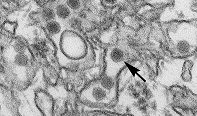

BOSTON – As public health officials warn that spring’s warmer temperatures may herald another increase of Zika virus infections in the Caribbean and North and South America, researchers around the world are racing to develop safe and effective measures to prevent the disease. In a review paper published today in the journal Immunity, a group of leading vaccine scientists – including Dan H. Barouch, MD, PhD, of Beth Israel Deaconess Medical Center (BIDMC) – outline advances in the hunt for a Zika vaccine and the challenges that still lie ahead.

The recent outbreak of the Zika virus in the Americas began in Brazil nearly two years ago. By February 2016, the World Health Organization had declared the epidemic a global public health emergency, based largely on the virus’ newly-established link to microcephaly and other major birth defects in babies born to infected mothers. The virus has also been associated with the neurologic disorder Guillain-Barré syndrome in adults.

Zika is a member of the flavivirus family of viruses, which includes West Nile virus, yellow fever virus, and dengue viruses, for which successful vaccines have been developed. Studies suggest that Zika-induced antibody responses may also cross-react with other flaviviruses, particularly dengue virus. Whether or not this antibody cross-reactivity may have clinical consequences is another consideration for Zika vaccines and requires further study.